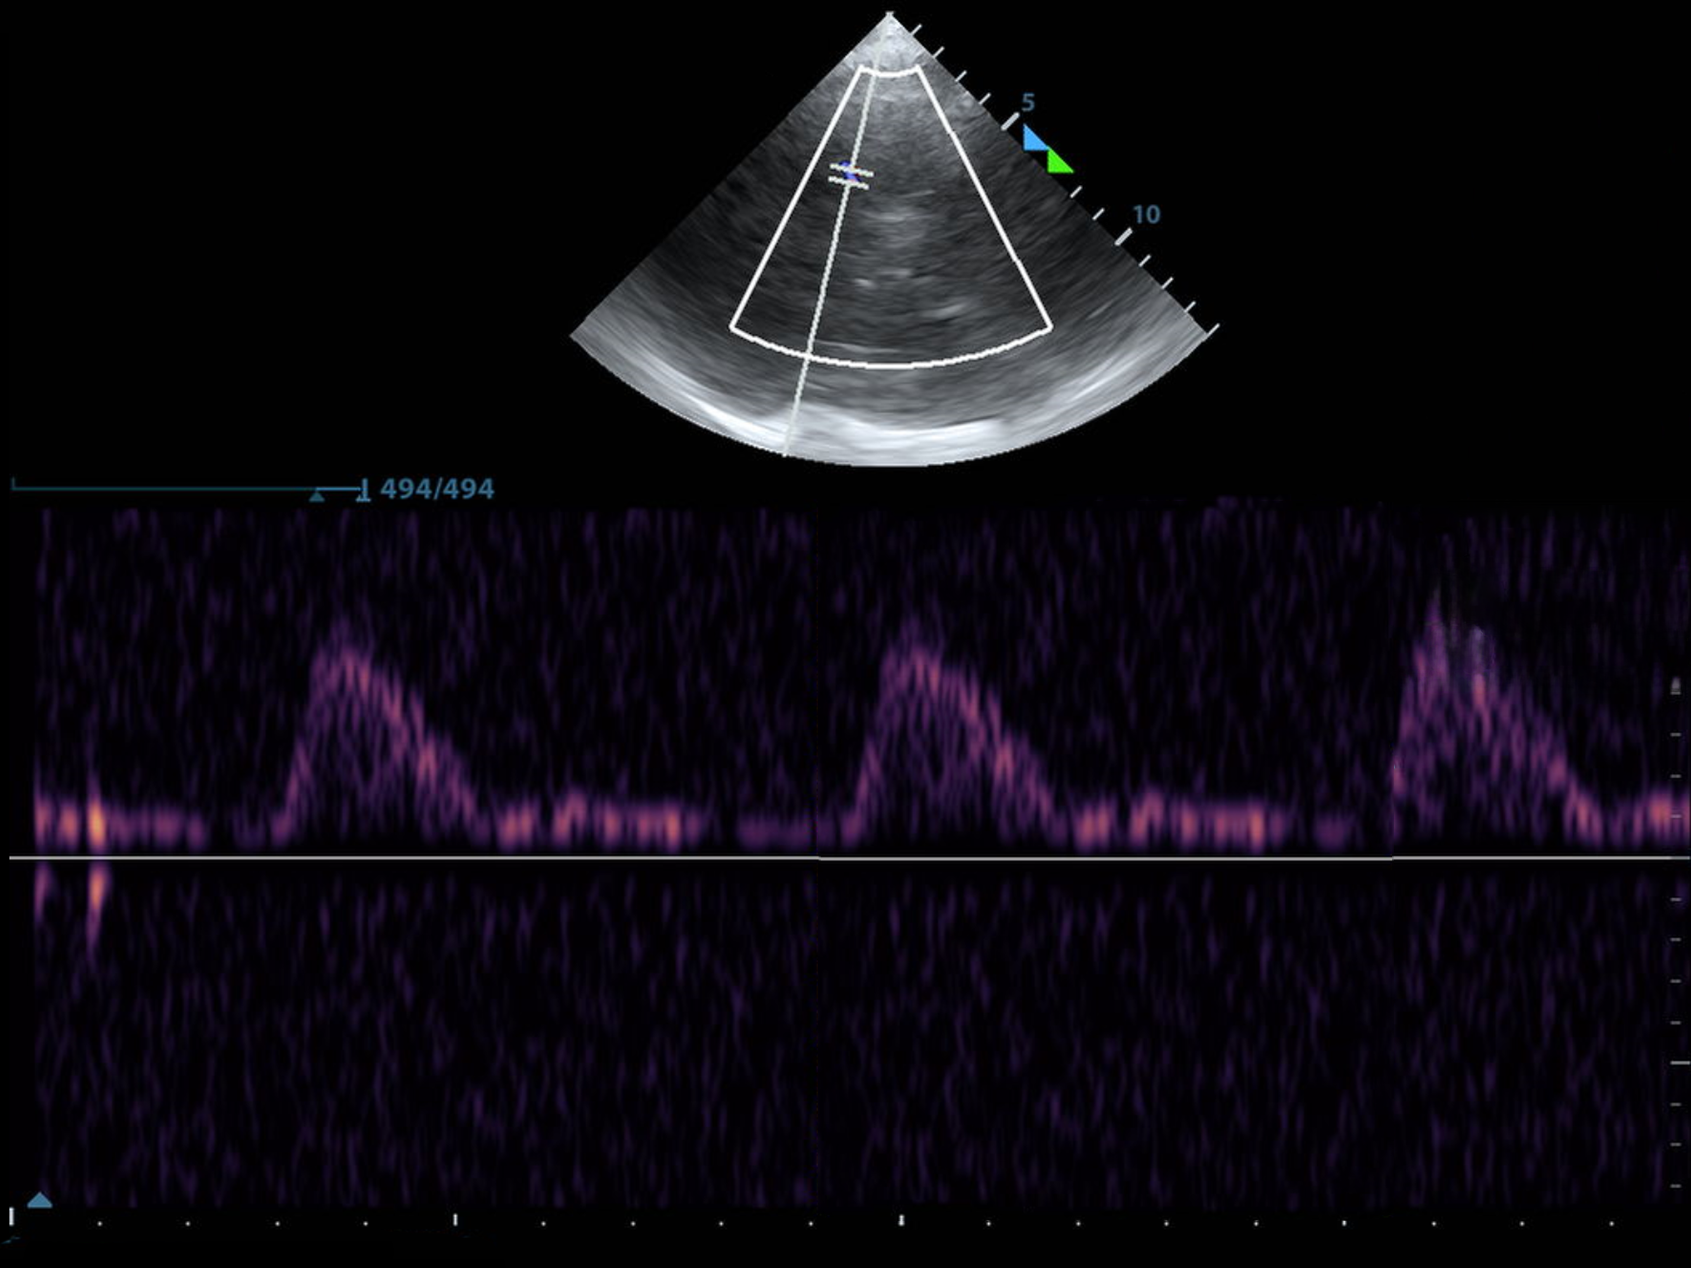

This is the Mesencephalon Plane. But relax, it's just the brainstem, and it will help us find everything else.

Specifically, it's the Midbrain, and this is the view you're most likely to start with if you put the probe down perfectly perpendicular to the temporal bone.

The Midbrain or Mesencephalon looks like the letter "M" turned sideways. Or a Butterfly.

I told you it looks like a butterfly.